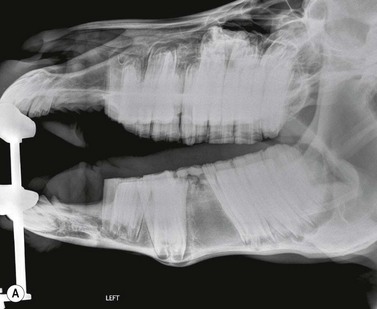

Dorsoventral projection (Figs 13.1213.13)

This view is quite easy to obtain in the sedated horse and is particularly useful for visualizing the ventral conchal sinus, nasal cavities, and nasal septum. Additionally, it can be used for evaluating maxillary/mandibular fractures; bony distortion of the maxilla associated with periapical infection of the rostral cheek teeth or intra-sinus masses. Laterally or medially displaced teeth and fractured maxillary teeth (particularly sagittal fractures) can also be visualized with this view; however, these abnormalities should be apparent during a thorough oral examination. The extremely dense bone of the hemimandibles makes it almost impossible to evaluate normally positioned mandibular cheek teeth using this projection.

An increased exposure is required for this projection compared to those used for lateral or lateral-oblique views of the skull. The X-ray beam is directed perpendicular to the dorsal plane of the head (which runs parallel to the hard palate) with the cassette held parallel with the ventral mandible and positioned as caudally as possible (Fig. 13.12). Because the mandibular cheek teeth rows are so close together (anisognathia), even a small degree of obliquity obscures one nasal cavity, ventral conchal sinus, and maxillary cheek teeth row and prevents accurate comparison of left and right maxillary sinus opacity; therefore, great care must be taken to ensure that the head is absolutely straight and the beam perpendicular to the dorsal plane. The centering point is in the midline of the dorsal aspect of the head at the level of the rostral aspect of the facial crests. Collimation of the primary beam should include the left and right lateral extents of the skull, the caudal aspects of the bony orbits and the diastemata, rostrally (Fig. 13.13).